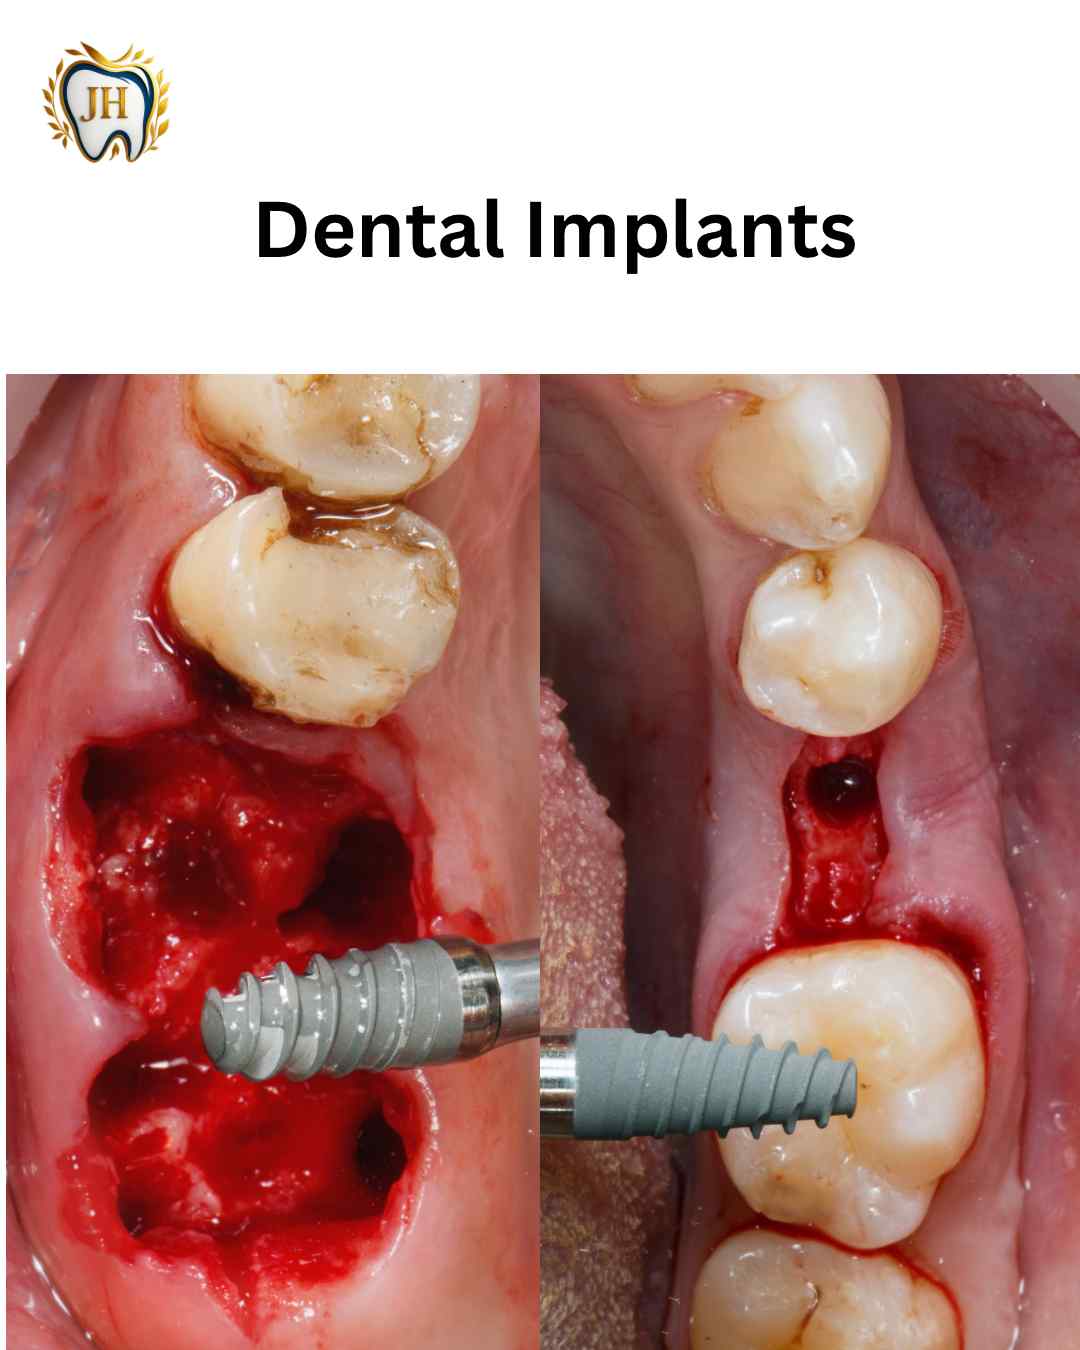

- Dental Implants